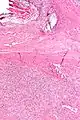

| Micrograph of a solitary fibrous tumor. H&E stain. | |

Solitary fibrous tumor - low magnification. H&E stain.

Solitary fibrous tumor - high magnification. H&E stain.